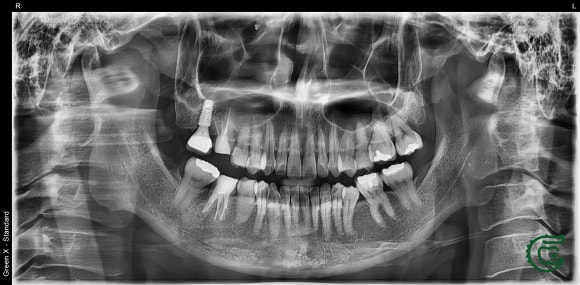

이 환자분은 인근 대학병원에서

오른쪽 위와 아래 어금니를 발치하라는

권유를 받았습니다.

그 이유는 치아 내부의 신경관이 극도로 막혀 있었기 때문이었습니다.

대학병원에서는 최신 현미경을 사용해 치료를 시도했지만,

신경관의 막힘으로 인해

더 이상의 치료 진행이 어렵다고 판단하여 발치를 권고한 상황이었죠.